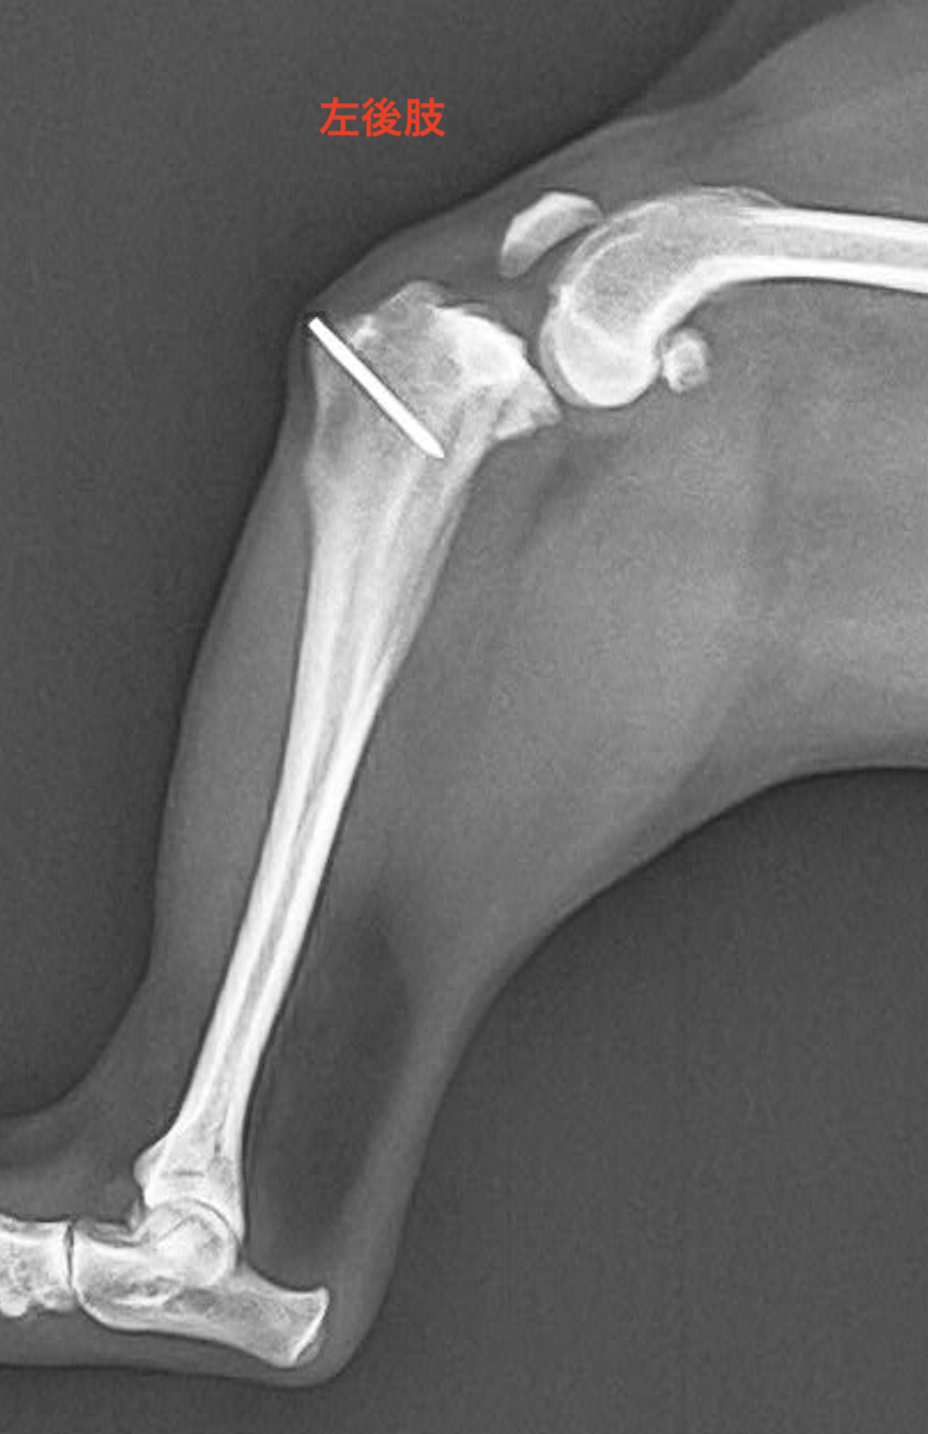

5歳チワワ

3年前に他院にてパテラのope済み

2.3日前から左後肢痛がる、着かないで歩いているとのことで来院されました。

各種検査から前十字靭帯断裂として手術を行いました。

術後1週間程度で問題なく歩けるようになりました。